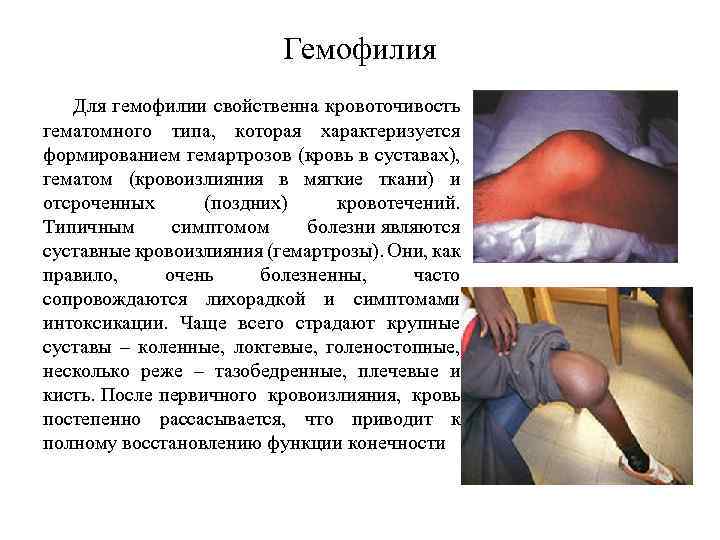

Гемофилия При многократных повторных повреждениях образуются фибриновые сгустки, которые откладываются на внутренней поверхности капсулы и хрящах, после чего прорастают соединительной тканью (рис. 11). В результате таких органических изменений тканей сустава, синовиальная полость облитерируется (суживается) и, как следствие патологического процесса, развивается анкилоз (сращение обеих костей, формирующих сустав) с последующим развитием хронических артрозов с деформацией и ограничением подвижности суставов, атрофией мышц и контрактурами, инвалидизирующих больных, заставляющих их пользоваться ортопедической коррекцией, костылями, инвалидными колясками. Возможны большие межмышечные, внутримышечные, поднадкостничные и забрюшинные гематомы, вызывающие иногда деструкцию подлежащей костной ткани (гемофилические псевдоопухоли), патологические переломы костей. Возможны упорные рецидивирующие желудочно-кишечные и почечные кровотечения

Гемофилия

гемофилия